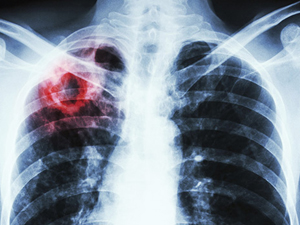

Один із ключових акцентів у Програмі медичних гарантій 2021 р. — наближення медичної допомоги до пацієнта. Прикладом того, як це відбувається, є новий пакет — «Супровід та лікування дорослих та дітей, хворих на туберкульоз, на первинному рівні медичної допомоги». Він поліпшує доступність та якість медичних послуг для пацієнтів з туберкульозом.

Таке надання протитуберкульозної допомоги наближає послугу до пацієнтів і забезпечує безперервність лікування. Тобто як тільки пацієнт перестає виділяти мікобактерію туберкульозу, що має лабораторне підтвердження, він може лікуватися амбулаторно та жити соціально повноцінним життям, перебуваючи не в лікарні, а в комфортних умовах вдома. А сімейний лікар контролює застосування пацієнтом ліків та результативність лікування.